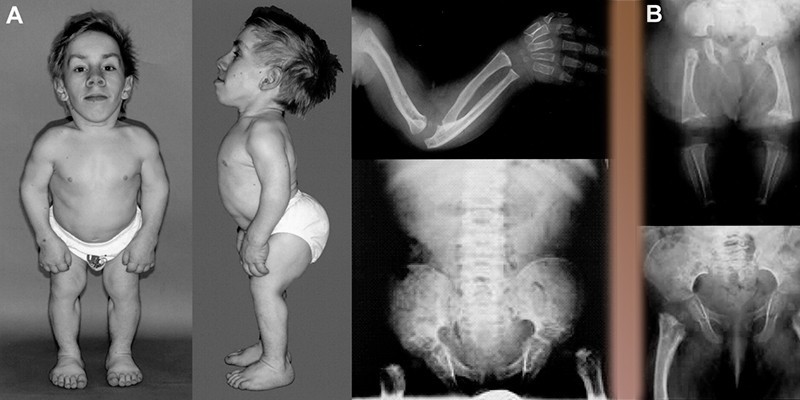

Как правило, при гипофизарном нанизме дети рождаются с нормальными показателями роста и веса. Задержка физического развития начинает проявляться к возрасту 2 лет и постепенно нарастает. Скорость роста у детей с карликовостью не превышает 1,5-2 см в год. Первыми признаками гипофизарного нанизма у детей являются очень тонкие, бледные кожные покровы и недоразвитие подкожно-жировой клетчатки при сохраненном достаточном питании.

Отличительной чертой заболевания у детей старше 2 лет являются сохраненные пропорции верхних, нижних конечностей, головы, туловища при их меньшем размере. Кроме того, отставание ребенка в росте сопровождается следующими признаками:

- маленькое круглое лицо;

- большой выступающий лоб;

- приплюснутая спинка носа;

- кожные покровы тонкие, бледные, сухие;

- непропорциональное отложение жира;

- слаборазвитые мышцы;

- недоразвитые половые органы.

При чистой форме

У взрослых людей, страдающих чистой формой гипофизарного нанизма, рост не превышает 135-140 см. Нередко наблюдается высокий тембр голоса, тонкие, редкие волосы на голове, слабое развитие подкожно-жирового слоя или ожирение, снижение остроты зрения, недоразвитие зубов, замедленный процесс окостенения, артериальная гипотония. Иногда наблюдается хрупкость костей, частые воспаления суставов.